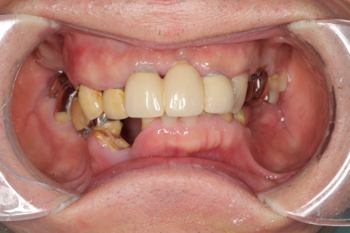

症例

50代男性。全顎的な虫歯と歯周病を治療した症例。

-

治療前 -

治療後

治療内容:噛み合わせの高さが低下し、ほぼすべての歯が虫歯と歯周病になっていたため、歯茎の治療を行った上で、審美的な被せものを製作しました。

治療期間:約12か月間

リスク・副作用:経年的な顎骨の吸収に対する調整の必要性、義歯を装着している違和感など